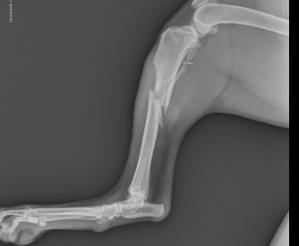

Radiographs – In juvenile dogs, changes can be very minimal. Classic radiographic signs include: osteoarthritis (anconeal ridge is an early sign), sclerosis (thickening) of the ulna, joint swelling and fragmentation of the medial coronoid process (33-50% visible on x-rays). OCD and UAP lesions typically will be evident on x-rays. It is standard to take three views of each elbow.

Patient with elbow dysplasia. Note the osteoarthritis present.

Patient with an ununited coronoid process.